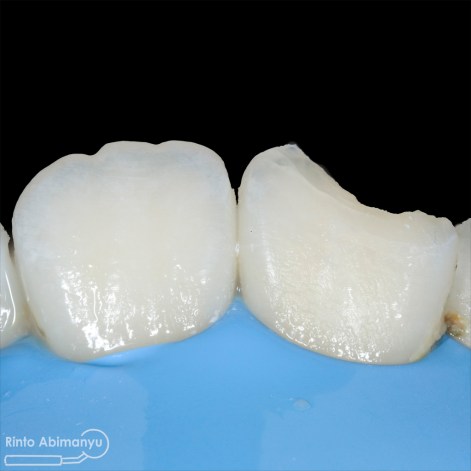

Pertama saya lakukan anestesi infiltrasi dan kemudian memasang rubber dam untuk isolasi daerah kerja, dilanjutkan pembersihan karies dan pembukaan kamar pulpa.. Pada kasus ini pengerjaan dilakukan langsung pada dua gigi…

Setelah akses ke kamar pulpa didapat, lalur dirapihkan agar arah masuk file dapat lurus, maka selanjutnya adalah proses cleaning and shaping… Panjang kerja diukur menggunakan apex locator Root ZX mini (Morita) dan preparasi saluran akar menggunakan i3 Gold (Denjoy)… Irigasi memakai larutan NaOCl 5,25% dan diaktivasi menggunakan waterpik dan tip endoactivator…

Setelah proses cleaning and shaping dilakukan trial gutta percha untuk melihat apakah kon utama yang akan kita gunakan pas dengan saluran akarnya…